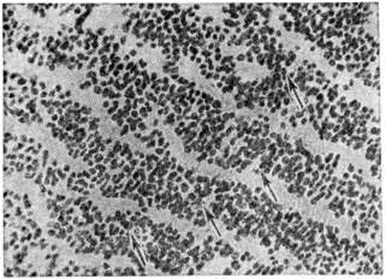

Макроскопически Медуллобластома имеет вид мягкого узла сероватого или серовато-розового цвета, довольно чётко отграниченного от окружающей ткани. Микроскопически опухоль состоит из густо расположенных недифференцированных клеток, образующих иногда своеобразные ритмические структуры в виде правильных или беспорядочных рядов, которые сравнивают с грядами и колоннами (рисунок 1). Особенно характерны микроскопические структуры в виде так называемый розеток, образованных кольцевидно расположенными опухолевыми клетками, отростки которых сходятся в центре розетки. Опухолевые клетки умеренно полиморфны, с многочисленными митозами. Наряду с гиперхромными мелкими округлыми ядрами в клетках Медуллобластома встречаются овальные и вытянуто-овальные, удлинённые, а также более крупные светлые округло-овальные ядра с чётким ядрышком. Строма опухоли скудная, с небольшим количеством преимущественно мелких, тонкостенных сосудов. Очаги некроза и кисты не типичны. Рост опухоли инфильтративный с прорастанием прилежащей ткани и мягкой оболочки мозга, нередко с вторичным врастанием из оболочки в подлежащую ткань. Медуллобластома метастазирует главным образом по ликворным пространствам, в мягкую оболочку и эпендиму желудочков мозга, в которых определяются плоские, сливающиеся между собой белесоватые узелки (рисунок 2), переходящие в диффузные разрастания. Иногда Медуллобластома даёт метастазы в лимф, узлы, кости, органы желудочно-кишечные тракта. |